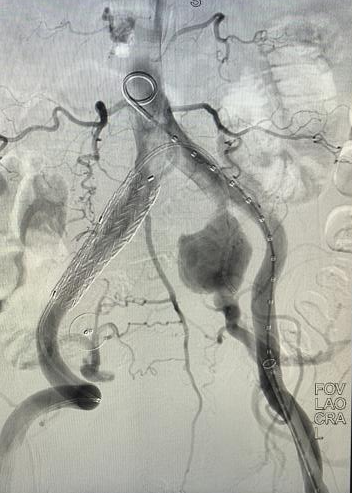

面对挑战,消化内科团队迅速启动多学科会诊。由血管外科驻桂专家王伦常博士、姚松良副主任医师及陈国兴硕士组成的攻坚小组,经全面评估后,决定优先通过微创手术处理动脉瘤。为了不影响后续的结肠手术,团队创新性地采用了PMEG技术,在局部麻醉下为患者施行了左侧髂内动脉瘤隔绝并重建术。术中,团队对支架进行了精准的台上改造与开窗,不仅成功隔绝了瘤体,更完美重建了左侧髂内动脉,保住了至关重要的血液供应。术后,患者恢复顺利,及时转入普外二病区(胃肠外科)完成了结肠肿瘤的治疗,现已康复出院。

术中团队对支架进行精准的台上改造与开窗

手术为患者完美重建左侧髂内动脉

心脏问题解决后,治疗的“接力棒”交到了血管外科团队手中。团队预先在腹主动脉支架上为副肾动脉开窗并标记,随后在术中精准定位,将导丝导管通过开窗口超选入副肾动脉并成功植入支架,最终造影显示,腹主动脉瘤被完全隔绝,副肾动脉血流通畅,且无内漏。术后,患者肾功能维持良好,平安出院。

患者术前、术后DSA检查结果对比